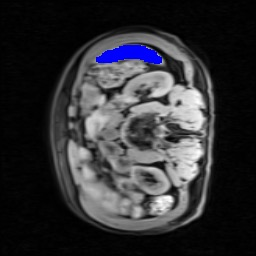

Transformers have made remarkable progress towards modeling long-range dependencies within the medical image analysis domain. However, current transformer-based models suffer from several disadvantages: (1) existing methods fail to capture the important features of the images due to the naive tokenization scheme; (2) the models suffer from information loss because they only consider single-scale feature representations; and (3) the segmentation label maps generated by the models are not accurate enough without considering rich semantic contexts and anatomical textures. In this work, we present CASTformer, a novel type of generative adversarial transformers, for 2D medical image segmentation. First, we take advantage of the pyramid structure to construct multi-scale representations and handle multi-scale variations. We then design a novel class-aware transformer module to better learn the discriminative regions of objects with semantic structures. Lastly, we utilize an adversarial training strategy that boosts segmentation accuracy and correspondingly allows a transformer-based discriminator to capture high-level semantically correlated contents and low-level anatomical features. Our experiments demonstrate that CASTformer dramatically outperforms previous state-of-the-art transformer-based approaches on three benchmarks, obtaining 2.54%-5.88% absolute improvements in Dice over previous models. Further qualitative experiments provide a more detailed picture of the model's inner workings, shed light on the challenges in improved transparency, and demonstrate that transfer learning can greatly improve performance and reduce the size of medical image datasets in training, making CASTformer a strong starting point for downstream medical image analysis tasks.